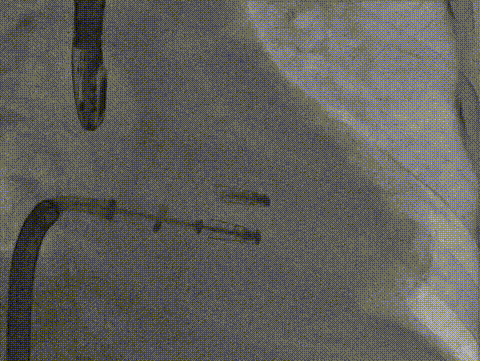

术中影像

房间隔穿刺

导引鞘置入左房

长宽夹打弯至瓣上

调整Orientation